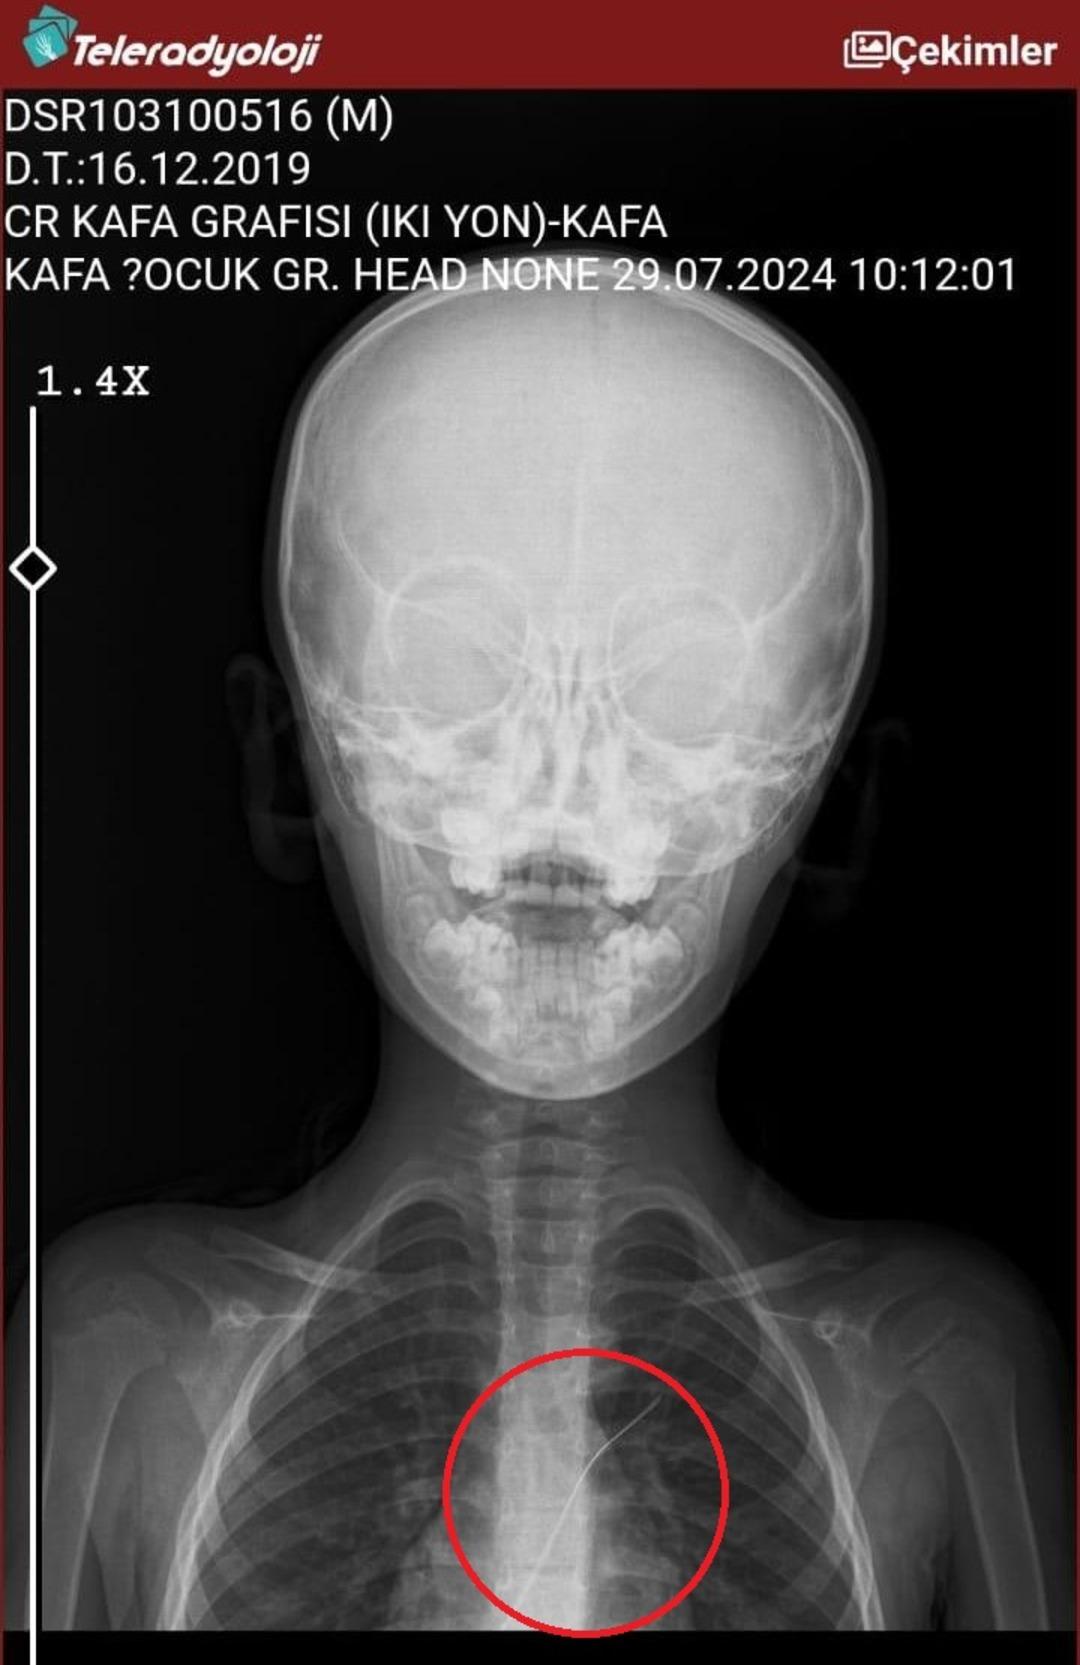

Seamore (37) ve Şaç’ta yaşayan Mehmet Ötün (40), Mayıs ayında bir parça salatalık yuttuktan sonra öksürük ve kusma şikayetleri gözlendiğinde Sernak Eyalet Hastanesine getirildi. Burada, ARAM gövdesinde yarıçap X ve manyetik rezonans görüntüleme unutuldu. Diyarbakir Gazi Yeşargil eğitim ve araştırma hastanesi jinekoloji ve ilave ARAM çocuk binasına yönlendirildi, 18 santimetrede 5.5 saatlik riskli ameliyat kaldırıldı. Postoperatif araştırmalarda, kateter kalp kapakına ve karaciğere zarar vermeye kararlıydı.